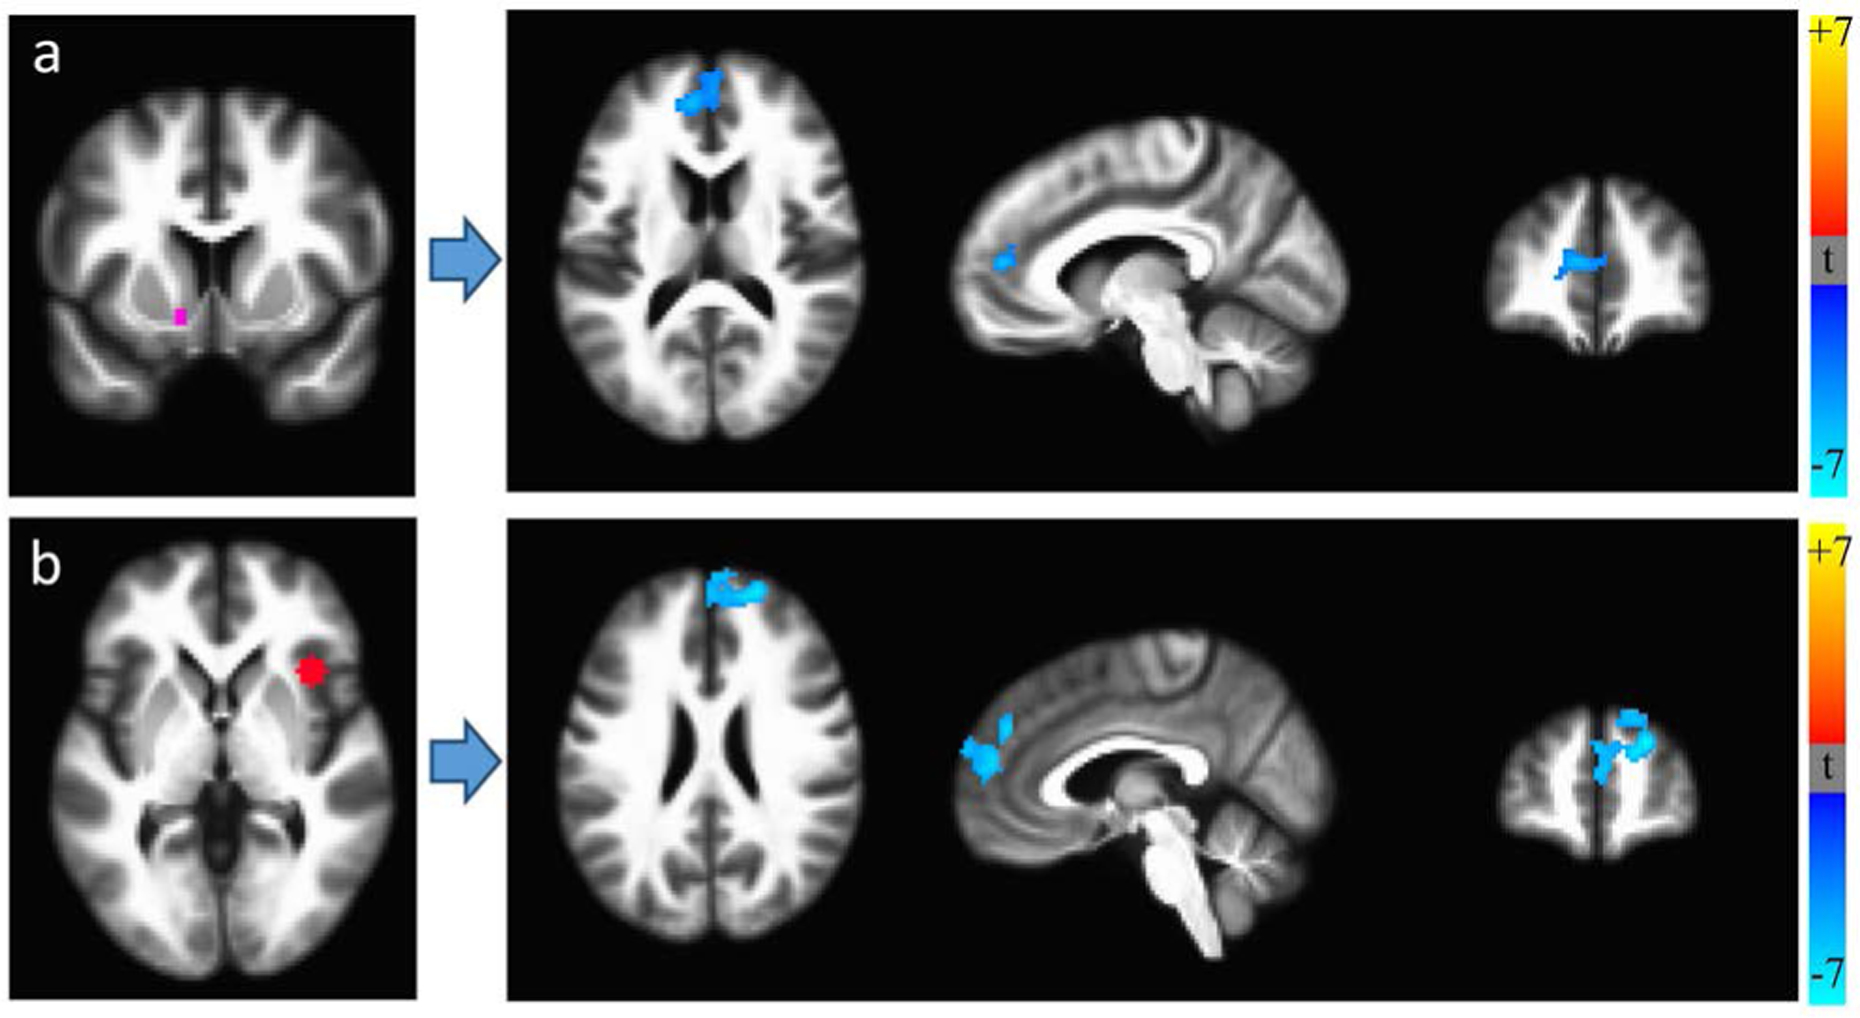

RSFC MRI scans were available for 21 HIV+ and 36 HIV− individuals (10 recent and 11 remote HIV+ cannabis users; 7 recent and 29 remote HIV− users). We first assessed RSFC differences between HIV+ and HIV− groups, applying multiple comparison corrections to achieve p < 0.05. Controlling for age, HIV+ participants had lower RSFC between the right anterior insula and mPFC and between the left NAcc and mPFC (Figure 1), consistent with task-related [ref. 63] and resting-state [ref. 64] [ref. 65] [ref. 66] decreases in frontostriatal functional connectivity in HIV.

Table 4 presents significant RSFC differences between recent and remote cannabis users for the HIV+ and HIV− groups. In HIV+ participants, recent use was associated with reduced RSFC (Figure 2), including that of the occipital cortex with the amygdala, putamen and ACC. HIV+ recent users also exhibited stronger caudate-precuneus and hippocampus-motor cortex RSFC, although these results were non-significant or did not survive multiple comparison corrections. Among HIV− individuals, recent users had lower insular RSFC compared with remote users; recent use was not associated with increased RSFC.